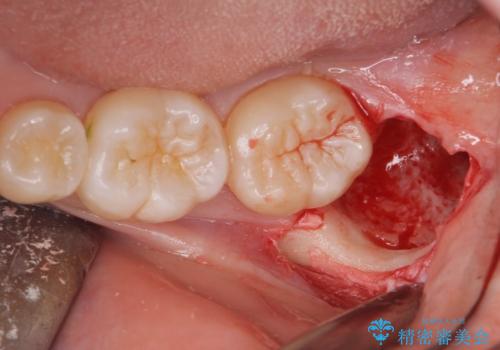

- 左上下親知らず抜きたいとの事で来院。

レントゲン、CTを撮影し安全を考慮して抜歯術を行いました。

無事に親知らず抜歯ができました。